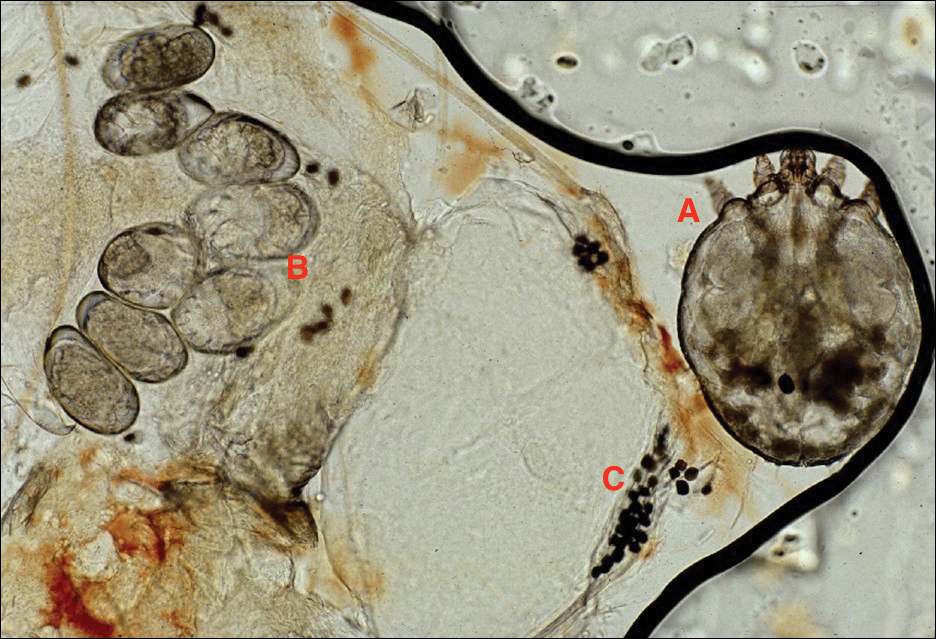

Adult females are 0.4-mm long and 0.3-mm wide, with males being smaller. Adult nymphs have 8 legs and larvae have 6 legs. Scabies mites are distinguishable from other arachnids by the position of a distinct gnathosoma and the lack of a division between the abdomen and cephalothorax.12 They are ovoid with a small anterior cephalic and caudal thoracoabdominal portion with hairlike projections coming off from the rudimentary legs. They can crawl as fast as 2.5 cm per minute on warm skin.2 The life cycle of the mite begins after mating: the male mite dies, and the female lays up to 3 eggs per day, which hatch in 3 to 4 days,2 in skin burrows within the stratum granulosum.12 Maturation from larva to adult takes 10 to 14 days.12 A female mite can live for 4 to 6 weeks and can produce up to 40 ova (Figure 1).